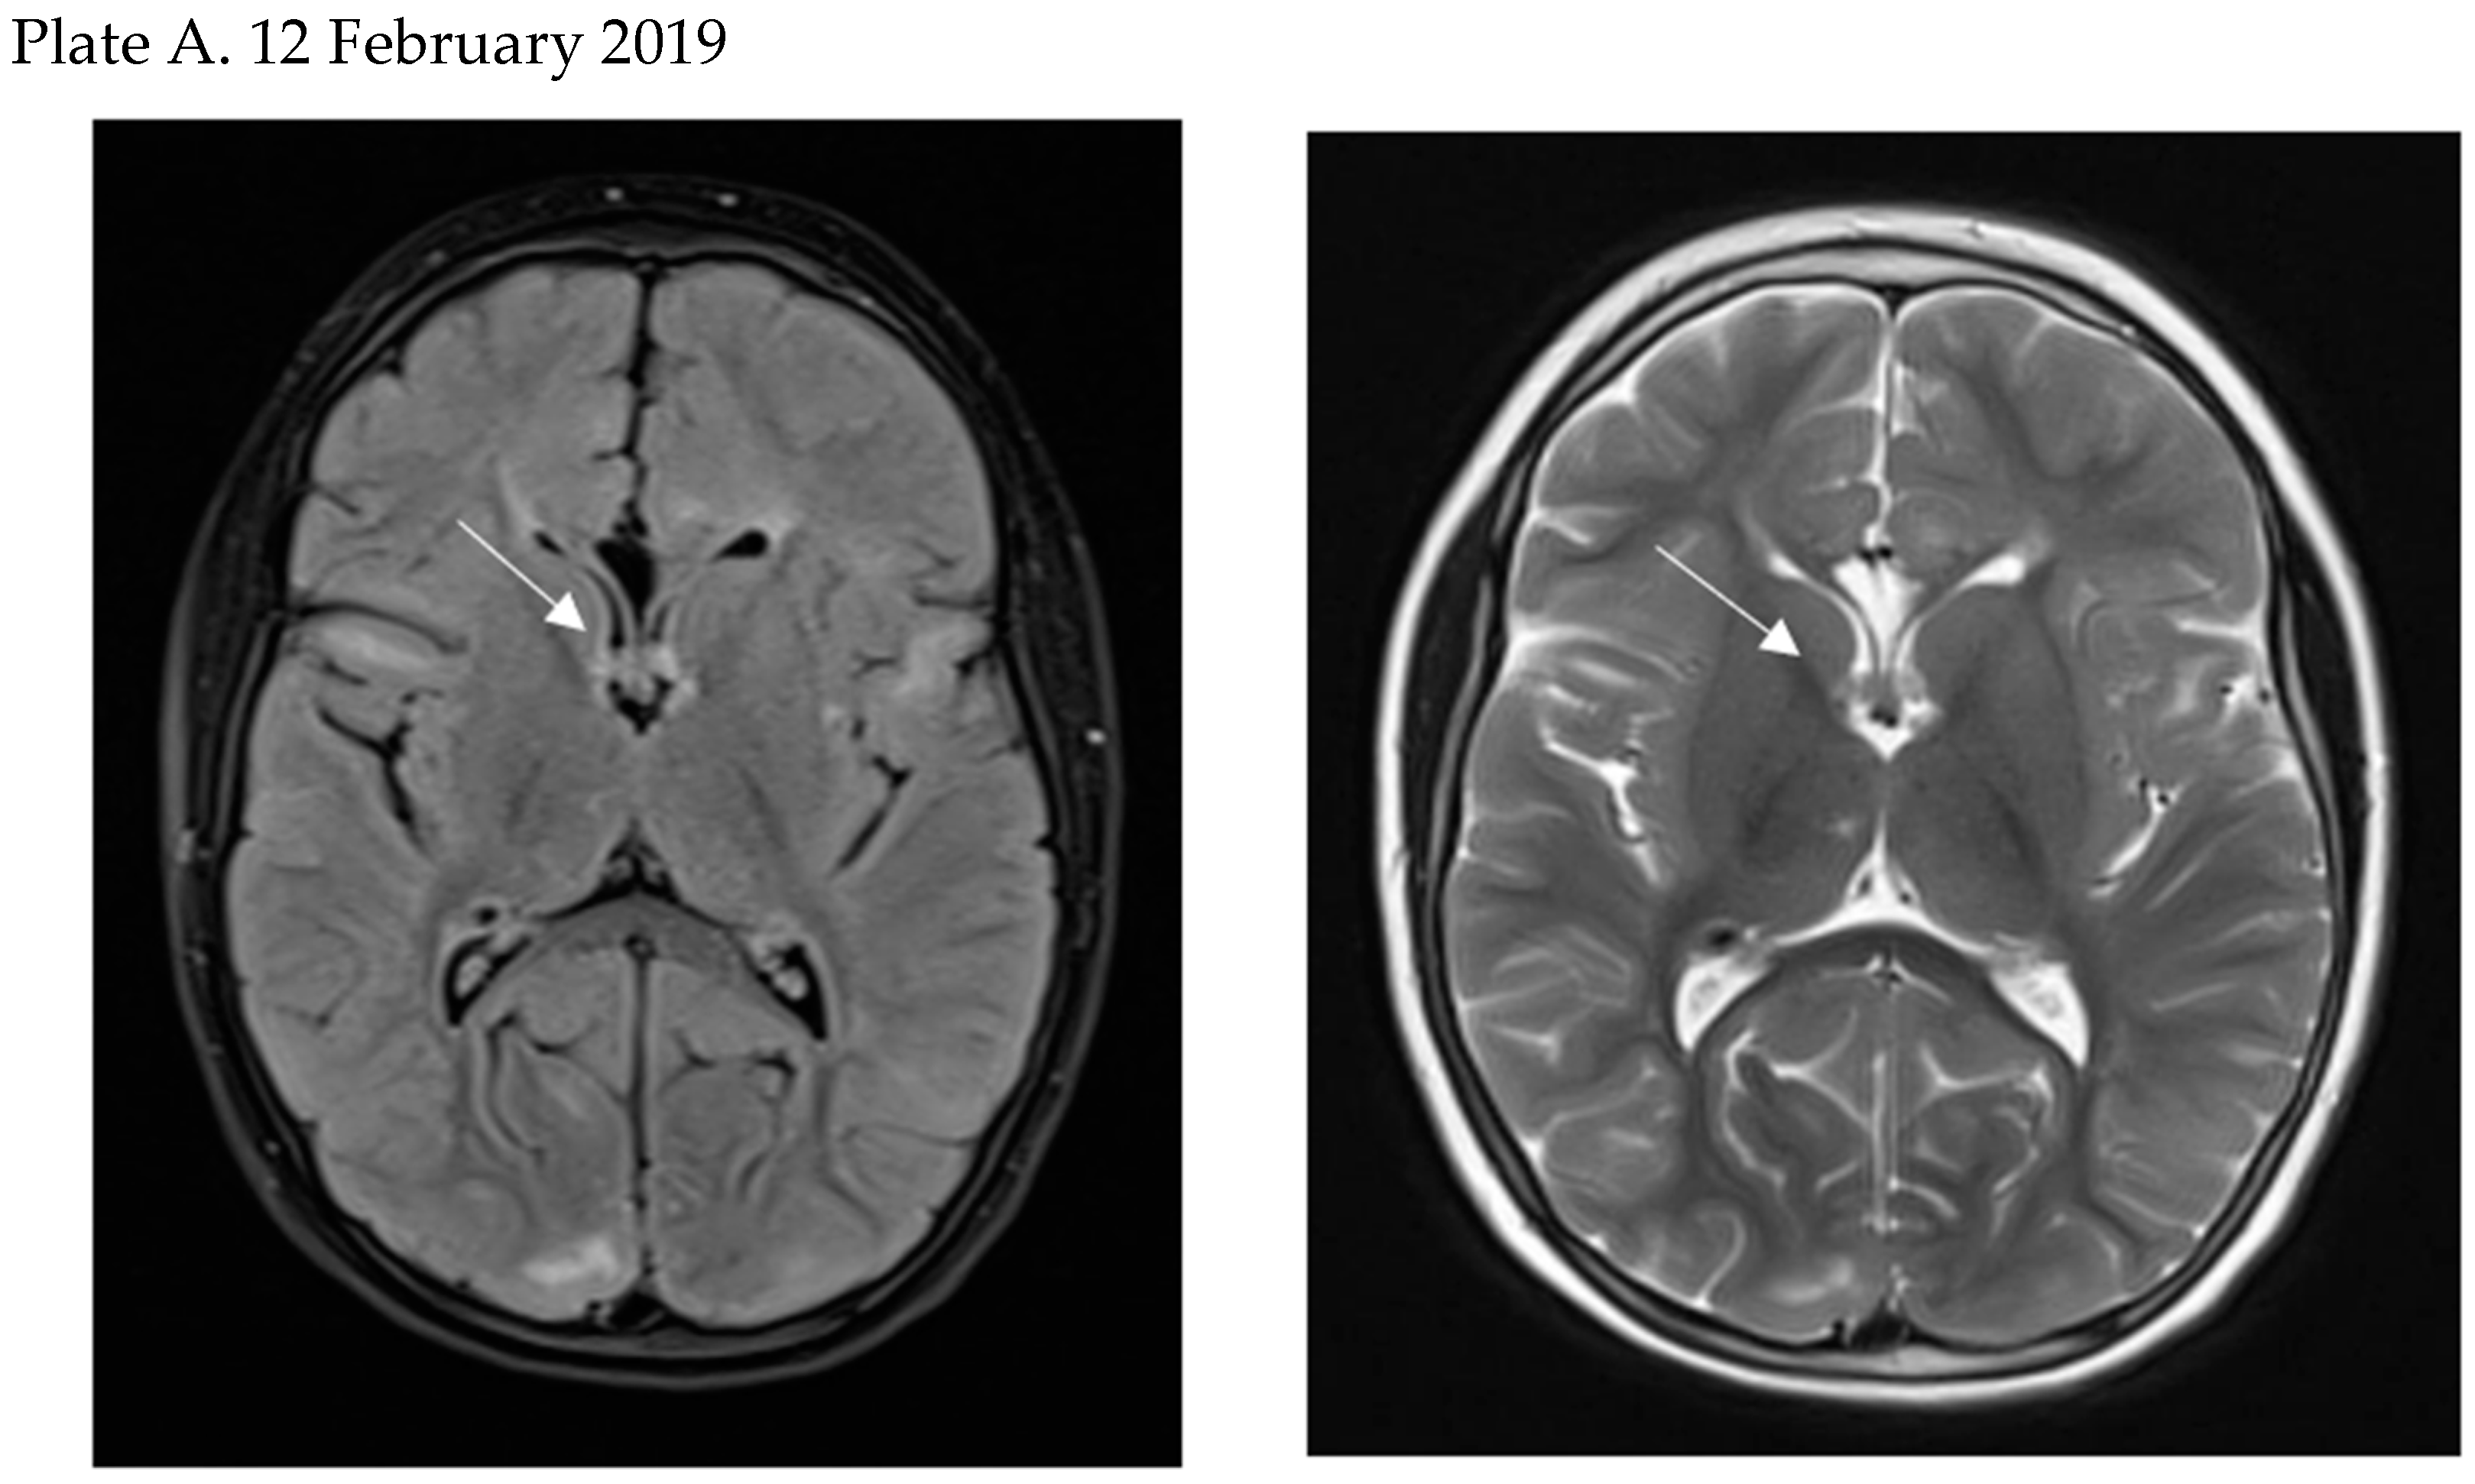

- Perek-Polnik, M.; Jozwiak, S.; Jurkiewicz, E.; Perek, D.; Kotulska, K. Effective everolimus treatment of inoperable, life-threatening subependymal giant cell astrocytoma and intractable epilepsy in a patient with tuberous sclerosis complex. Eur. J. Paediatr. Neurol. 2012, 16, 83–85. [Google Scholar] [CrossRef] [PubMed]